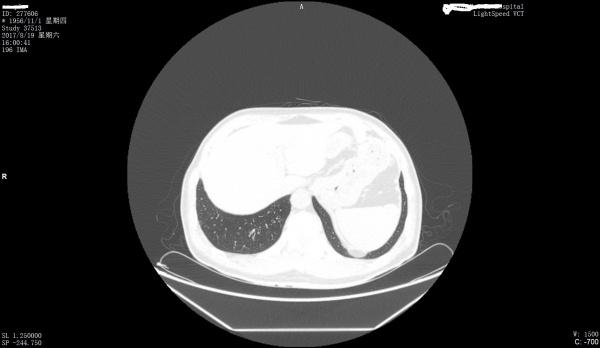

看看是否左膈肌出现胸腹膜裂孔疝

最好把纵膈窗也传一下

第一上传图片少,第2目前来看只能是疑似。